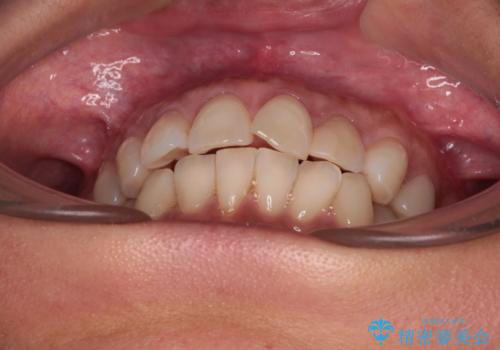

- 目立つ銀歯やむし歯、前歯のデコボコを気にして来院された患者様です。

デコボコはある程度改善できれば良いとのことでしたので、インビザラインの廉価版を用いて矯正治療を行うこととしました。

むし歯治療は、症状のある歯を矯正治療前に処置し、概ね歯列が整ったところで残りのは全て処置し、最後にインビザラインで歯列を仕上げることで、無駄なく治療を進めて行くこととしました。